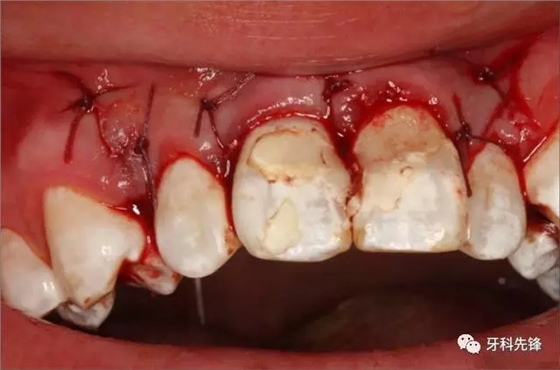

圖11.清理牙槽窩、隔濕。并用MTA封閉根尖。

圖12.拔牙創(chuàng)放置膠原蛋白海綿

圖13.縫合

圖14.縫合完畢的口內(nèi)照片